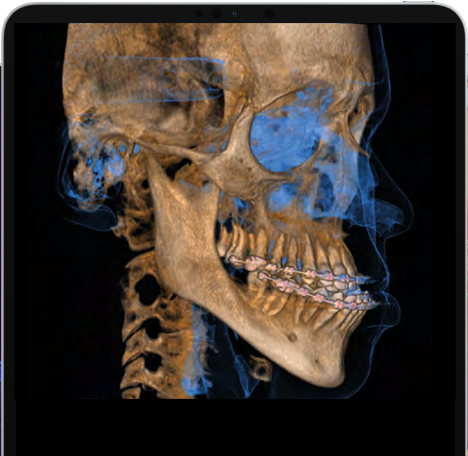

Compartilhamento extensivo e poder de processamento com a plataforma de imagem final.

O software NNT da NewTom oferece todas as funções necessárias para executar, processar, exibir e compartilhar exames 2D e 3D. O NNT também oferece diferentes modos de aplicação e funções especificamente destinadas a planejar o melhor tratamento para aplicações de implantologia, endodontia, periodontia e radiologia, bem como cirurgia maxilofacial.